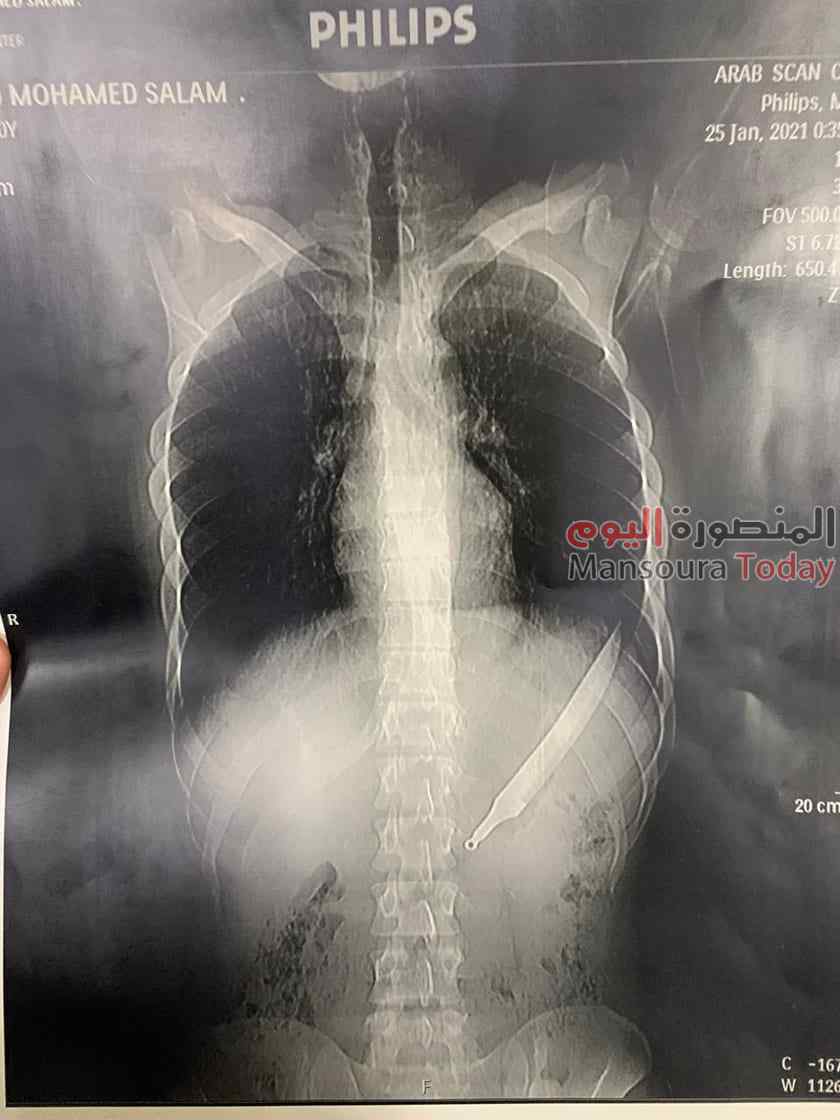

أوضح الدكتور إيهاب الدسوقى استشارى الجراحة بمستشفى المنصورة الدولى تفاصيل ابتلاع شاب سكينة مطبخ قائلا أن ابتلاع الأجسام الغريبة وارد ويحدث كثيرا لكن لأول مرة نشاهد شخص يبتلع سكينة وكانت حالة مثيرة للقلق.

وأشار الدكتور إيهاب فى تصريح خاص ل “المنصورة توداى” أن المريض وصل لمستشفى المنصورة الدولى مريض من أجا 20 عاما مع أسرته يعانى من آلام شديدة، وبسؤاله أكد أنه ابتلع سكينة أثناء الأكل وتم عمل الأشعات اللازمة ولم نتخيل أنها سكينة كاملة لكننا تخيلنا أنه بلع جزء من السكين، واستغربنا بعد نتيجة الأشعة، وكان لابد من التأكد من عدم وجود مشاكل بسبب ابتلاعها فى البلعوم أو المرئ أثناء نزولها وهذا يعطى إيحاء أنها ابتلعت بالإتجاه المعاكس لأنها لو ابتلعت بالإتجاه الحاد كانت ستتسبب فى مشاكل كثيرة وقد تؤدى إلى وفاته، لأن طولها 28 سم.

كان الدكتور سعد مكي وكيل وزارة الصحة بالدقهلية أعلن عن نجاح فريق طبي في انقاذ حياة مريض ابتلع سكين مطبخ كبير حيث حضر المريض للمستشفى الدولي يعاني من آلام شديدة بالبطن وبعمل الاشعات والفحوصات تبين وجود جسم غريب وتمكن الفريق الطبي من إجراء عملية جراحية لاستخراج الجسم الغريب (سكين مطبخ) وقد تكللت العملية بالنجاح وخرج المريض بحالة مستقرة.